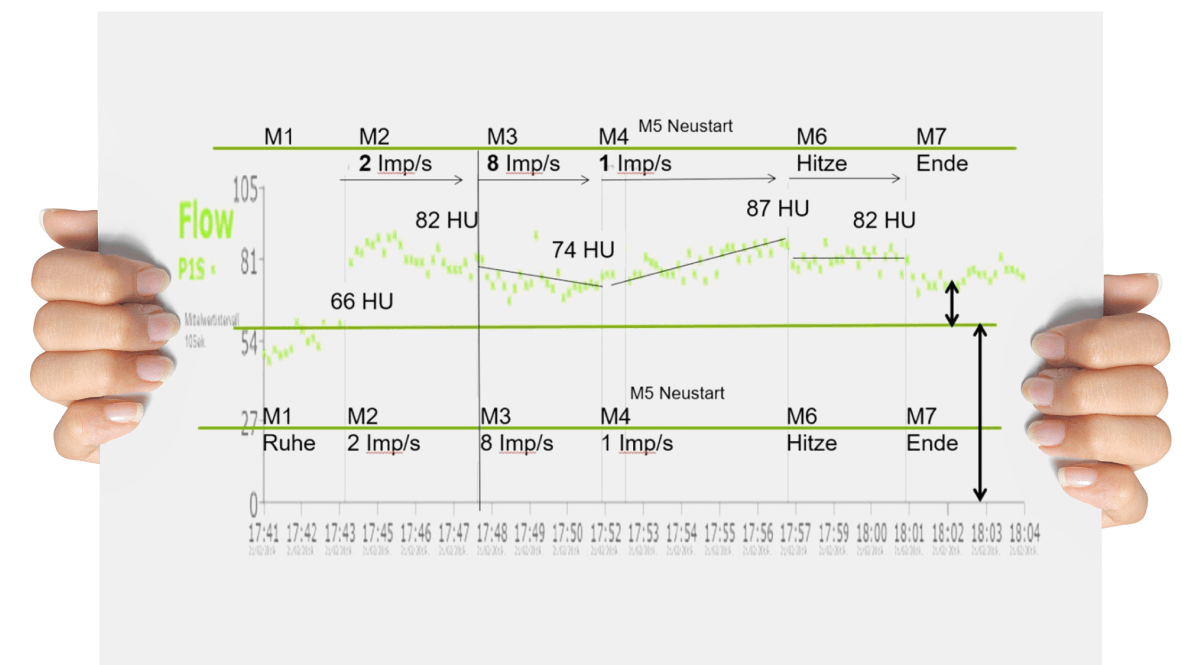

Selitykset kivun vähenemiselle ioni-induktion käytön jälkeen vaihtelevat keskushermoston β-endorfiinin lisääntymisestä motorisen päätylevyn hyperpolarisaatioon ja paikallisen verenkierron edistämiseen. On mielenkiintoista, että nykyiset julkaisut kivunhoidosta PEMF:n avulla viittaavat yhä useammin typpimonoksidijärjestelmän vaikutuksiin mikroverenkiertoon toden näköisimp änä syynä. Vastaavia havaintoja teki myös Dr. univ. med. Dr. rer. Nat. Manfred Hartard:

Mikroverenkierron mittaus LEA-Medizintechnikin (Giessen) laser-Doppler-spektrofotometrialla (O2C) korkean PEMF-intervention aikana papimi® -laitteen avulla. Lähde: Sportärztezeitung 05/2019 edition